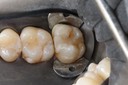

Mark Chun #17 pre-op

Mark Chun #17 prep

Mark Chun #17 model

Mark Chun #17 casting